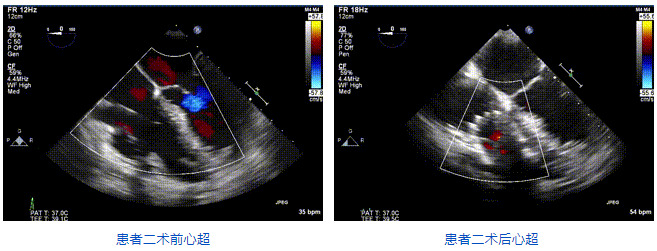

2021年12月24日,復(fù)旦大學(xué)附屬中山醫(yī)院葛均波院士團(tuán)隊(duì)成功應(yīng)用LuX-Valve Plus為一例極重度三尖瓣反流(TR)合并房顫、房缺的患者完成了經(jīng)血管三尖瓣置換術(shù),這是在前基礎(chǔ)上,本周完成的第三例經(jīng)血管三尖瓣置換手術(shù),葛均波院士、周達(dá)新教授等與心外科魏來(lái)教授、賴顥教授,心超室的潘翠珍教授、李偉教授及麻醉科的郭克芳教授共同完成了本周手術(shù),均獲得圓滿成功!患者術(shù)后超聲顯示無(wú)TR,臨床癥狀明顯改善。本周手術(shù)的成功也為L(zhǎng)uX-Valve Plus救治性臨床研究添上了濃墨重彩的一筆。

三例患者入院后,葛均波院士團(tuán)隊(duì)周達(dá)新教授、潘文志教授、張?jiān)床┦?、陳莎莎博士及心超室的潘翠珍教授、李偉教授?duì)患者的情況進(jìn)行詳細(xì)評(píng)估和討論,最終決定為三例患者選擇LuX-Valve Plus40mm、50mm和50mm型號(hào)的瓣膜進(jìn)行手術(shù)治療。手術(shù)后即刻拔除氣管插管,術(shù)后患者三尖瓣反流癥狀得到顯著改善,復(fù)查心超結(jié)果顯示人工三尖瓣瓣膜支架固定穩(wěn)定,瓣葉關(guān)閉形態(tài)未見異常,未見明顯反流。